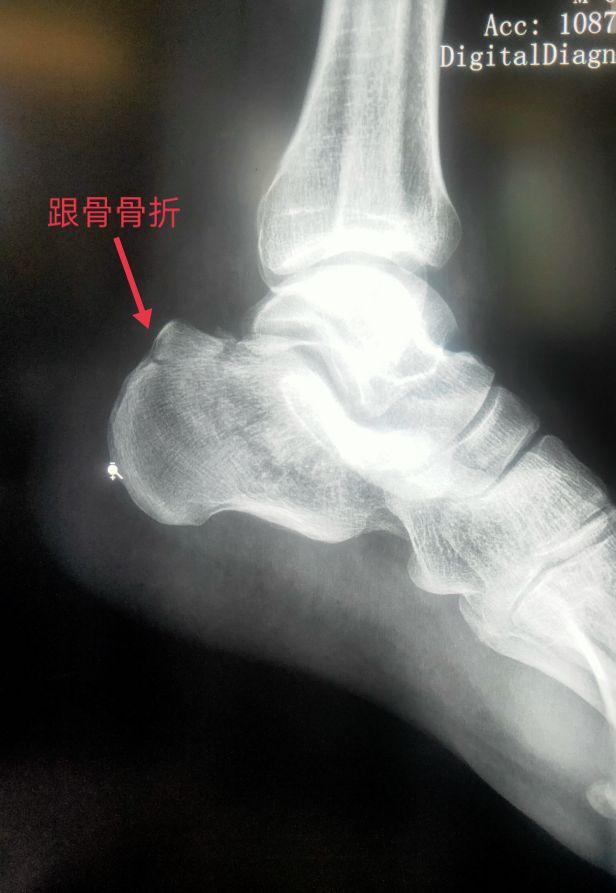

四、踝关节部位的骨折、脱位X线片

车祸、摔跤、跌倒都会造成骨折或脱位。以踝部、距骨、跟骨多见。

脚踝是哪个部位图解,脚踝是哪个部位图解视频(学习《X线读片指南》骨、关节系统——踝关节)